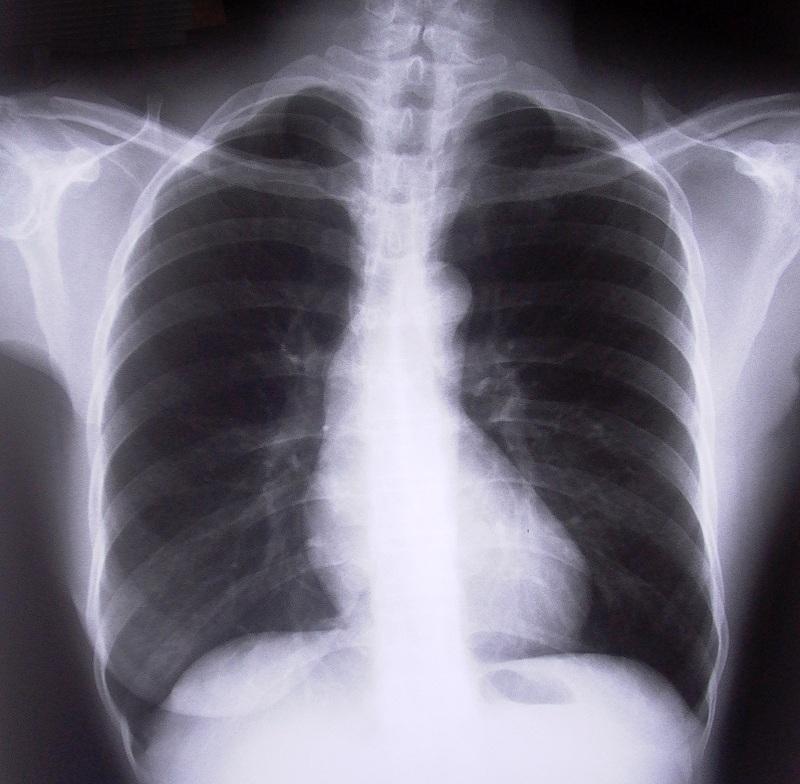

Se sofreu um grande golpe ou um acidente e se suspeita que tem uma ou mais costelas quebradas, deverá ir imediatamente a um hospital para fazer uma análise oportuna e confirmar o diagnóstico, pois será necessária a opinião médica para confirmar se a fratura coloque em perigo os pulmões ou qualquer outro órgão.

Dependendo da gravidade da fratura terá de ficar sob observação médica para garantir que os seus pulmões e coração não estão em perigo. As complicações neste tipo de casos residem fundamentalmente na dificuldade para respirar que alguns pacientes podem ter, se não é o seu caso então poderá ser-lhe dada alta e continuar com os cuidados em casa.